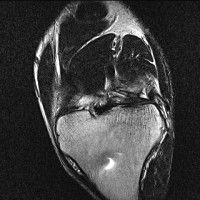

무릎 mri 간단히 봐주실 수 있으시나요 ㅠㅠ

안녕하세요 8년전 십자인대 수술하고 최근 무리한 운동에 무릎 불편감이 생겨서

mri 찍었습니다.

진단결과는 첫 찍은 병원에서 활액막염 이라는 진단을 받았습니다. 혹시 봐주실 수 있으실까요?

올라온 MRI가 단편적이라서 정확한 진단에 어려움이 있지만 십자인대에는 큰 이상이 있지는 않은것 같으며, 무릎관절내 물이 있는 것으로 보아 활액막염의 진단이 맞을 것 같습니다.

하지만 단편적인 영상이기 때문에 촬영병원에서 정확한 판독지 등을 받으시는 것이 좋겠습니다.